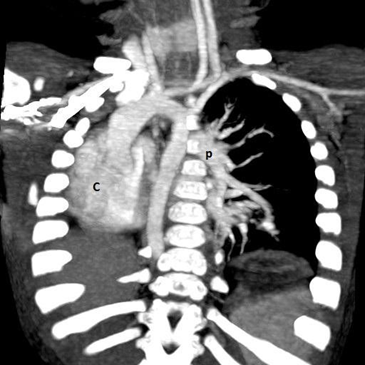

Figure 1.3 CT angiography (reconstructed 3D).

P: Lt. pulmonary artery and branches, C: dextroposition of heart – displaced in to the Rt. Hemi thorax